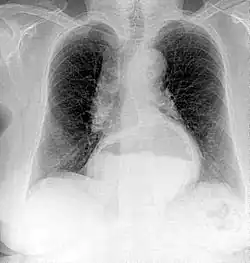

Projectional radiography is the practice of producing two-dimensional images using X-ray radiation. Bones contain a high concentration of calcium, which, due to its relatively high atomic number, absorbs X-rays efficiently. This reduces the amount of X-rays reaching the detector in the shadow of the bones, making them clearly visible on the radiograph. The lungs and trapped gas also show up clearly because of lower absorption compared to tissue, while differences between tissue types are harder to see.[115]

Projectional radiographs are useful in the detection of pathology of the skeletal system as well as for detecting some disease processes in soft tissue. Some notable examples are the very common chest X-ray, which can be used to identify lung diseases such as pneumonia, lung cancer, or pulmonary edema, and the abdominal x-ray, which can detect bowel (or intestinal) obstruction, free air (from visceral perforations), and free fluid (in ascites). X-rays may also be used to detect pathology such as gallstones (which are rarely radiopaque) or kidney stones which are often (but not always) visible. Traditional plain X-rays are less useful in the imaging of soft tissues such as the brain or muscle. One area where projectional radiographs are used extensively is in evaluating how an orthopedic implant, such as a knee, hip or shoulder replacement, is situated in the body with respect to the surrounding bone. This can be assessed in two dimensions from plain radiographs, or it can be assessed in three dimensions if a technique called '2D to 3D registration' is used. This technique purportedly negates projection errors associated with evaluating implant position from plain radiographs.[116]